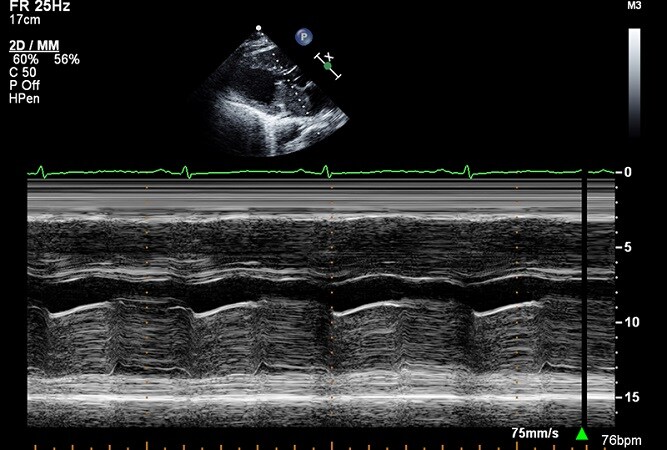

CV Imaging